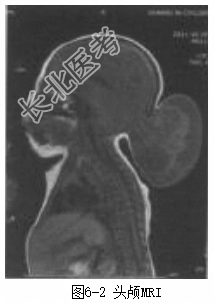

患儿男性,1月龄。因“出生后发现枕部肿物1个月”入院。患儿出生后家长即发现其枕部有一肿物,约“核桃”太小,随患儿生长,肿物逐渐增大,家长发现患儿哭闹对肿物可略增大,安静睡眠时又略缩小,至今无破溃、流液。发病以来,患儿食欲好,大小便正常,不伴有呕吐、肢体抽搐等情况。体格检查T37℃,R36次/min,P116次/min,BP78/神志清楚,头围40cm,前囟平软,枕部中线处可见一大小约5cm×5cm×4cm的肿物,表面无毛发生长,质软,囊性感,无压痛。双眼球活动灵活,双鼻唇沟对称,颈部无抵抗。心、肺、腹未见明显异常体活四肢肌力4级、肌张力正常。生理反射存在,病理征阴性。辅助检查头颅CT(图6-1)示枕骨局部缺损,枕部脑膨出;头颅MRI(图6-2)示枕部脑膜脑膨出。

诊断枕部脑膨出。治疗完善术前准备,行三大常规、凝血七项、血生化、胸部X线、心脏超声、腹部超声等术前检查。除了上述常规的术前检查外,还需行如下专科检查和处理:(1)行头颅CT检查,了解颅骨发育有无异常。(2)行头颅磁共振静脉成像(MRV)检查,了解静脉窦位置及与膨出物的关系。(3)背部有无毛发生长或肿物、瘘管、色素沉着、血管瘤等,必要时行脊髓MRI检查。